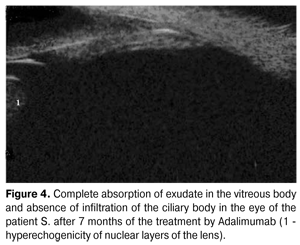

Considering the presence of relapse during the treatment with methotrexate, in five months Adalimumab 20 mg 1 time in two weeks subcutaneously was prescribed additionally. The patient S. already on the second week of treatment showed clinical improvement: morning stiffness has disappeared, range of motion in the joints significantly increased. During the control ophthalmological study there was noted disappearance of the circumcorneal flush and photophobia, precipitates on endothelium of the cornea have reabsorbed. According to UBM in 4 months exudate in prebasal sections of the vitreous body has reabsorbed and its quantity in basal sections has decreased. Against the background of this therapy a complete relief of inflammatory process and significant improvement in visual acuity has been achieved. After 7 months of the usage of Adalimumab an exudate in basal and prebasal sections of the vitreous body has reabsorbed completely (Fig. 4), inflammatory infiltration of the ciliary body was not observed.